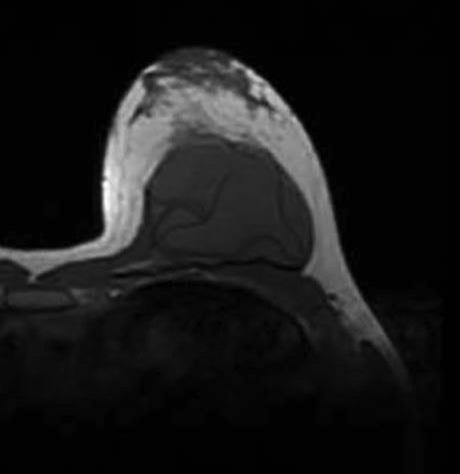

En la imagined la izquierda se puede apreciar el signo del linguini dentro de la protasis. Este signo se ve en la resonancia nuclear magnética y es la comprobación de ruptura de la prótesis.